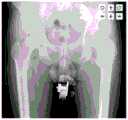

图3-4是根据本申请实施例提供的一种确定临床中的实际截骨线位置的示意图;3-4 are schematic diagrams of determining the actual position of the osteotomy line in the clinic according to an embodiment of the present application;

具体的,“根据股骨柄假体的旋转中心和在髋关节的X线图像识别过程中确定的髋臼杯的旋转中心确定截骨线位置”为通过移动股骨柄假体,将股骨柄假体的旋转中心与之前计算的髋臼杯旋转中心位置重合,得到股骨柄假体实际位置。沿股骨柄假体的涂层位置可确定临床中的实际截骨线位置,如图3-4所示。图3为移动股骨柄假体到预定位置,使股骨柄假体的旋转中心与之前计算的髋臼杯旋转中心位置重合,图4为根据股骨柄假体的外形确定截骨线位置。Specifically, “determine the position of the osteotomy line according to the rotation center of the femoral stem prosthesis and the rotation center of the acetabular cup determined during the X-ray image recognition of the hip joint” is to move the femoral stem prosthesis to move the femoral stem prosthesis The center of rotation of the acetabular cup coincides with the previously calculated center of rotation of the acetabular cup to obtain the actual position of the femoral stem prosthesis. The location of the coating along the femoral stem component can determine the actual position of the osteotomy line in clinical practice, as shown in Figure 3-4. Figure 3 shows moving the femoral stem prosthesis to a predetermined position so that the rotation center of the femoral stem prosthesis coincides with the previously calculated acetabular cup rotation center position, and Figure 4 shows the position of the osteotomy line determined according to the shape of the femoral stem prosthesis.